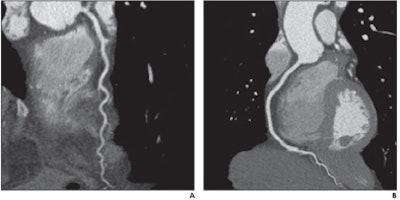

| Effect of ASIR on image signal and noise. CT angiographic images show ascending aorta in 48-year-old man. Images were reconstructed using both FBP (left) and 40% ASIR (right). Window width and level are the same for each. Signal and noise measurements were taken from 1-cm2 circular region of interest in same location. Signal was similar between FBP and ASIR (718.6 HU versus 719.3 HU, respectively), whereas noise decreased between FBP and ASIR (52.3 HU versus 38.5 HU). All images republished with permission of the American Roentgen Ray Society. |